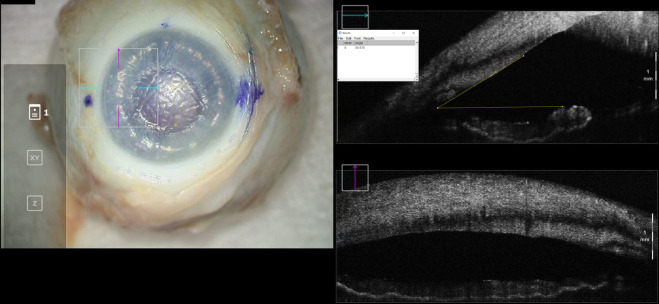

Introduction: During endothelial keratoplasty, anterior chamber gas is titrated to a desired fill, which is difficult to optimize by visualization alone. This study evaluates how an anterior chamber gas fill correlates with intraocular pressure (IOP) and iris-angle configuration as identified by optical coherence tomography (OCT).

Methods: Eleven cadaveric eyes were studied in three configurations: baseline, air-fill just spanning limbus-to-limbus ("full-fill"), and air-fill maximally filling the anterior chamber ("overfill"). At each configuration, IOP was measured by Tonopen and iris-angle was determined by analyzing OCT images.

Results: No differences in IOP or irisangles were identified between baseline and full-fill configurations (p=0.113 and p=0.152, respectively). When compared to overfill configuration, differences in IOP and iris-angles were identified for baseline (p<0.001 and p=0.001, respectively) and full-fill configuration (p=0.001 and p=0.039, respectively).

Discussion: These findings highlight that en-face visualization of full-fill may not be indicative of IOP elevation. A significant difference in IOP and iris-angle exists between full-fill and overfill configurations. Intraoperative OCT can serve as a useful surrogate to identify the extent of fill.